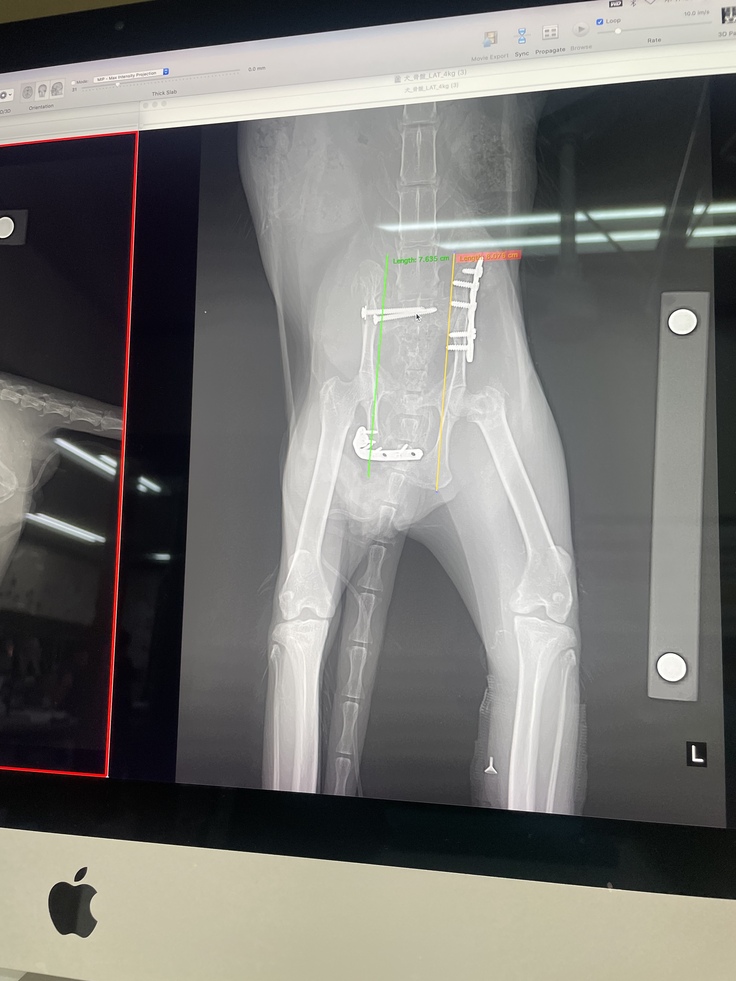

手術後レントゲン

よそよそしくし、シャーと警戒はしているものの僕の手からチュールをあげ全て完食してくれて嬉しかったです。手術の日程も決まりました。大変大掛かりな手術になる事から旭川の動物病院の方で手術することになりました。

7/27日退院

↓手術費用、7月17日から7月27日分の入院費